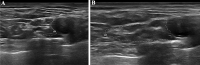

Axonal polyneuropathy is the main feature of hereditary transthyretin amyloidosis (ATTRv). Nerve morphological abnormalities have been reported, but longitudinal changes have never been assessed. We performed a prospective widespread nerve ultrasound evaluation and nerve cross-sectional area (CSA) was compared with baseline data in both ATTRv patients and pre-symptomatic carriers. Thirty-eight subjects were evaluated (mean follow-up 17.1 months), among them 21 had polyneuropathy while 17 were pre-symptomatic carriers. CSA significantly increased at brachial plexus in both groups (p = 0.008 and p = 0.012) pointing to progressive brachial plexus enlargement as a longitudinal biomarker of both disease progression and disease occurrence in pre-symptomatic carriers.